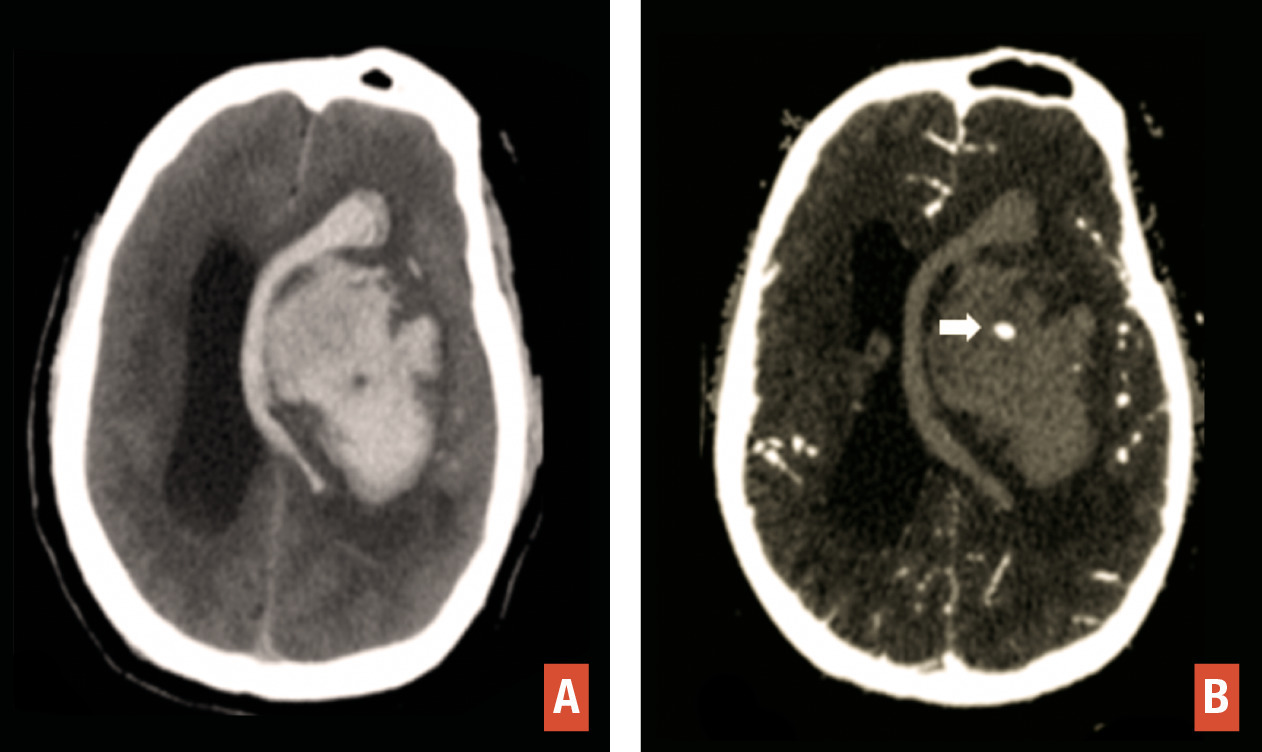

En TDM comme en IRM, l’hématome cérébral se traduit par une masse, de volume et de topographie variables, avec œdème périlésionnel. En tomodensitométrie, l’hématome aigu est hyperdense spontanément. En IRM, il est hyperintense en séquence T2/FLAIR avec hyposignaux le plus souvent périphériques en T2* (fig. 5 ). L’aspect hétérogène, la présence d’îlots hématiques satellites et le « spot sign » visible après injection traduisent un saignement actif avec risque de majoration rapide en volume (fig. 6 ).

La cause la plus fréquente des hématomes cérébraux non traumatiques est la microangiopathie hypertensive. Les hématomes en lien avec cette cause sont le plus souvent profonds (noyaux gris centraux, protubérance) et s’associent volontiers à une leucopathie vasculaire, des lacunes et des micro-saignements profonds. Un bilan d’imagerie, à la recherche d’une autre origine, est réalisé en cas d’absence d’hypertension artérielle, d’âge jeune ou d’hématome lobaire.5 L’angio-TDM recherche une malformation vasculaire sous-jacente.

En IRM, le bilan comporte des séquences injectées dynamiques, une séquence de susceptibilité magnétique et une séquence volumique T1 sans et avec injection de gadolinium. L’injection dynamique permet une visualisation précoce des structures veineuses en cas de fistule ou de malformation artérioveineuse. Ce bilan peut être complété par une artériographie cérébrale en cas d’hématome lobaire non traumatique sans cause retrouvée en IRM. La séquence 3D T1 avec injection de gadolinium cherche à éliminer une tumeur sous-jacente et à s’assurer de la perméabilité des sinus veineux. Un thrombus veineux apparaît sous la forme d’un hyposignal linéaire sur les séquences de susceptibilité magnétique (T2* ou SWI) et d’un défaut de rehaussement d’un sinus veineux ou d’une veine corticale sur les séquences après injection (fig. 7 ). En cas d’hématome lobaire du sujet âgé, ces séquences recherchent des anomalies évocatrices d’angiopathie amyloïde telles que des microsaignements (« microbleeds ») de disposition périphérique, des séquelles d’hématomes et une sidérose corticale superficielle.

En IRM, le bilan comporte des séquences injectées dynamiques, une séquence de susceptibilité magnétique et une séquence volumique T1 sans et avec injection de gadolinium. L’injection dynamique permet une visualisation précoce des structures veineuses en cas de fistule ou de malformation artérioveineuse. Ce bilan peut être complété par une artériographie cérébrale en cas d’hématome lobaire non traumatique sans cause retrouvée en IRM. La séquence 3D T1 avec injection de gadolinium cherche à éliminer une tumeur sous-jacente et à s’assurer de la perméabilité des sinus veineux. Un thrombus veineux apparaît sous la forme d’un hyposignal linéaire sur les séquences de susceptibilité magnétique (T2* ou SWI) et d’un défaut de rehaussement d’un sinus veineux ou d’une veine corticale sur les séquences après injection (